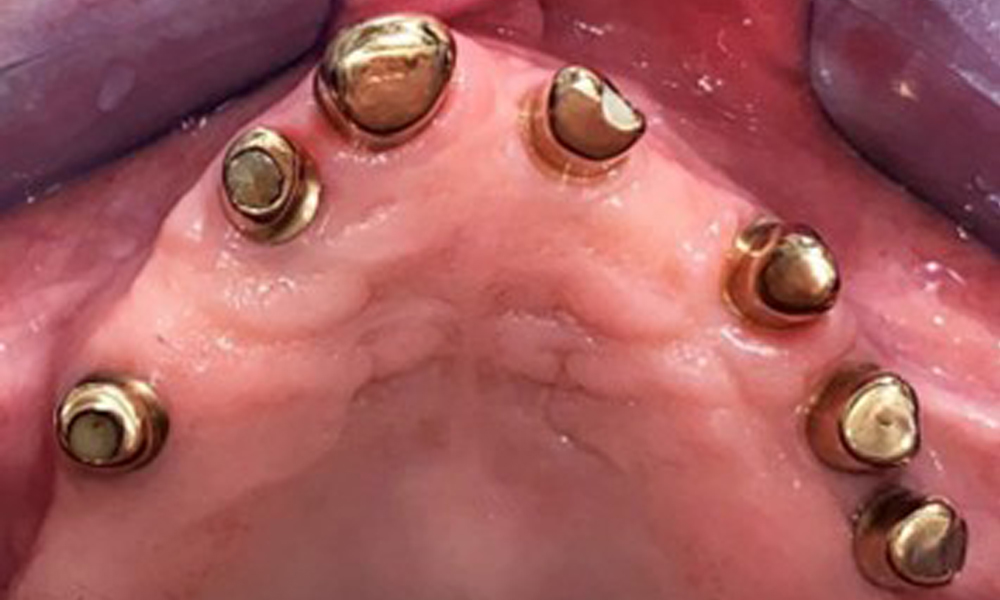

Der dentale Befund stellt sich wie folgt dar: Kombinierte herausnehmbare Implantat- und zahngetragene Teleskoparbeit auf Implantaten 15, 13, 21, 23, 24, 25 und Zahn 11 (Abb. 1, Abb. 2, Abb. 3). Im Unterkiefer ist die Patientin mit einem festsitzenden Zahnersatz versorgt. 37–34 sowie 45–47 haben suffiziente Brücken (Abb. 4). Kronenränder sind intakt, aktive kariöse Läsionen sind nicht vorhanden. An Zahn 43 zeigt sich eine Compositefüllung mit Randspalt. Im Unterkiefer liegen Rezessionen mit freiliegender Wurzeloberfläche zwischen 1 – 3 mm vor. Dies trifft auch für 11 zu.

Okklusalansicht: Oberkiefer mit Zahn- und implantatgetragenen Teleskopen.

Abb. 2: Okklusalansicht: Oberkiefer mit Zahn- und implantatgetragenen Teleskopen.